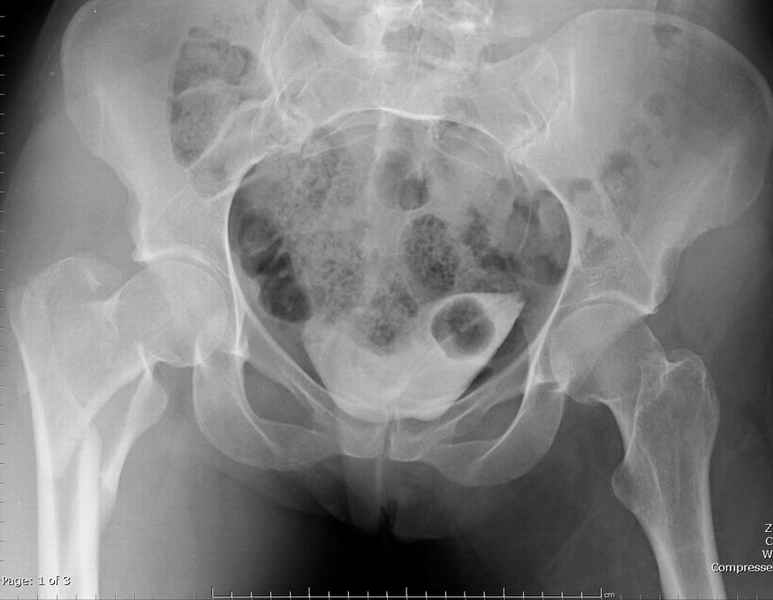

Centromedullary and Cephalomedullary По классификация Seinsheimer

(1978) V- на основе количества фрагментов-нестабильный.

По Russel- Taylor Type II – Piriformis is not intact Type IIB – lesser

troch is not intact перелом с вовлечением двух кортексов и

вертела - нестабильный,

Деформирующие силы: В проксимальной части бедра

FAbER- Флексия, Абдукция, Наружная Ротация.

В Дистальном отделе Аддукторы ведут к Варусному положению.

Деформирующие силы усложняют закрытую репозицию и фиксацию Перед операцией КТ для определения степени вовлечения пириформис фосса.

Ap pelvis Rt sub-intra trochanteric Fracture, AP Rt hip, Postop Blade Fixation